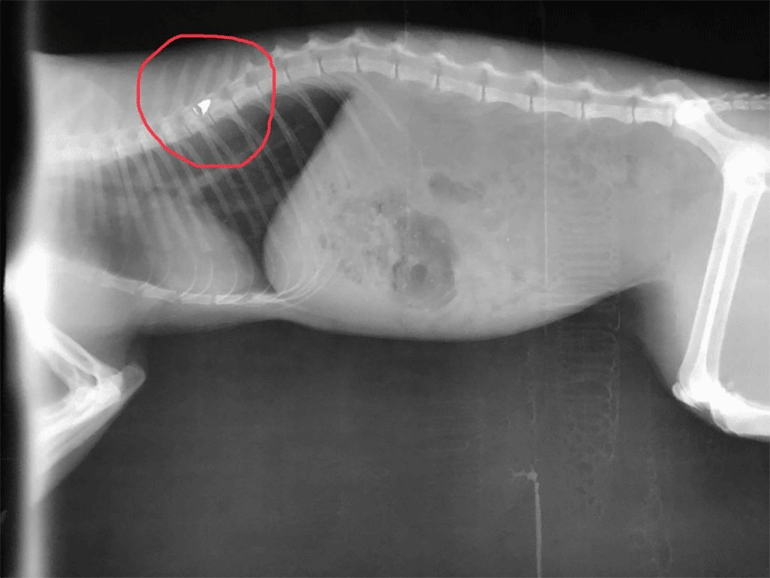

Το άτυχο ζώο δέχθηκε τη σφαίρα στην σπονδυλική στήλη, όπως δείχνουν και οι ακτινογραφίες που κατατέθηκαν στο Δικαστήριο. Ο παράλυτος πλέον γάτος, φιλοξενείται προσωρινά, στο σπίτι του ανθρώπου που βρέθηκε μπροστά στο συμβάν ενώ άγνωστο παραμένει το μέλλον του, αφού θα χρειαστεί χειρουργείο.

Ήδη ο φιλοζωικός σύλλογος έχει απευθυνθεί σε ιατρείο στη Λάρισα προκειμένου οι κτηνίατροι να αποφανθούν για την κατάσταση του ζώου αλλά και το πως θα μπορούσε να αφαιρεθεί η σφαίρα που έχει σφηνωθεί στην ραχοκοκαλιά του. Αυτό βέβαια σημαίνει ότι θα πρέπει να υπάρξει χρόνος, χρήματα και εθελοντές, αφού η αποκατάσταση του δεν δείχνει εύκολη υπόθεση.